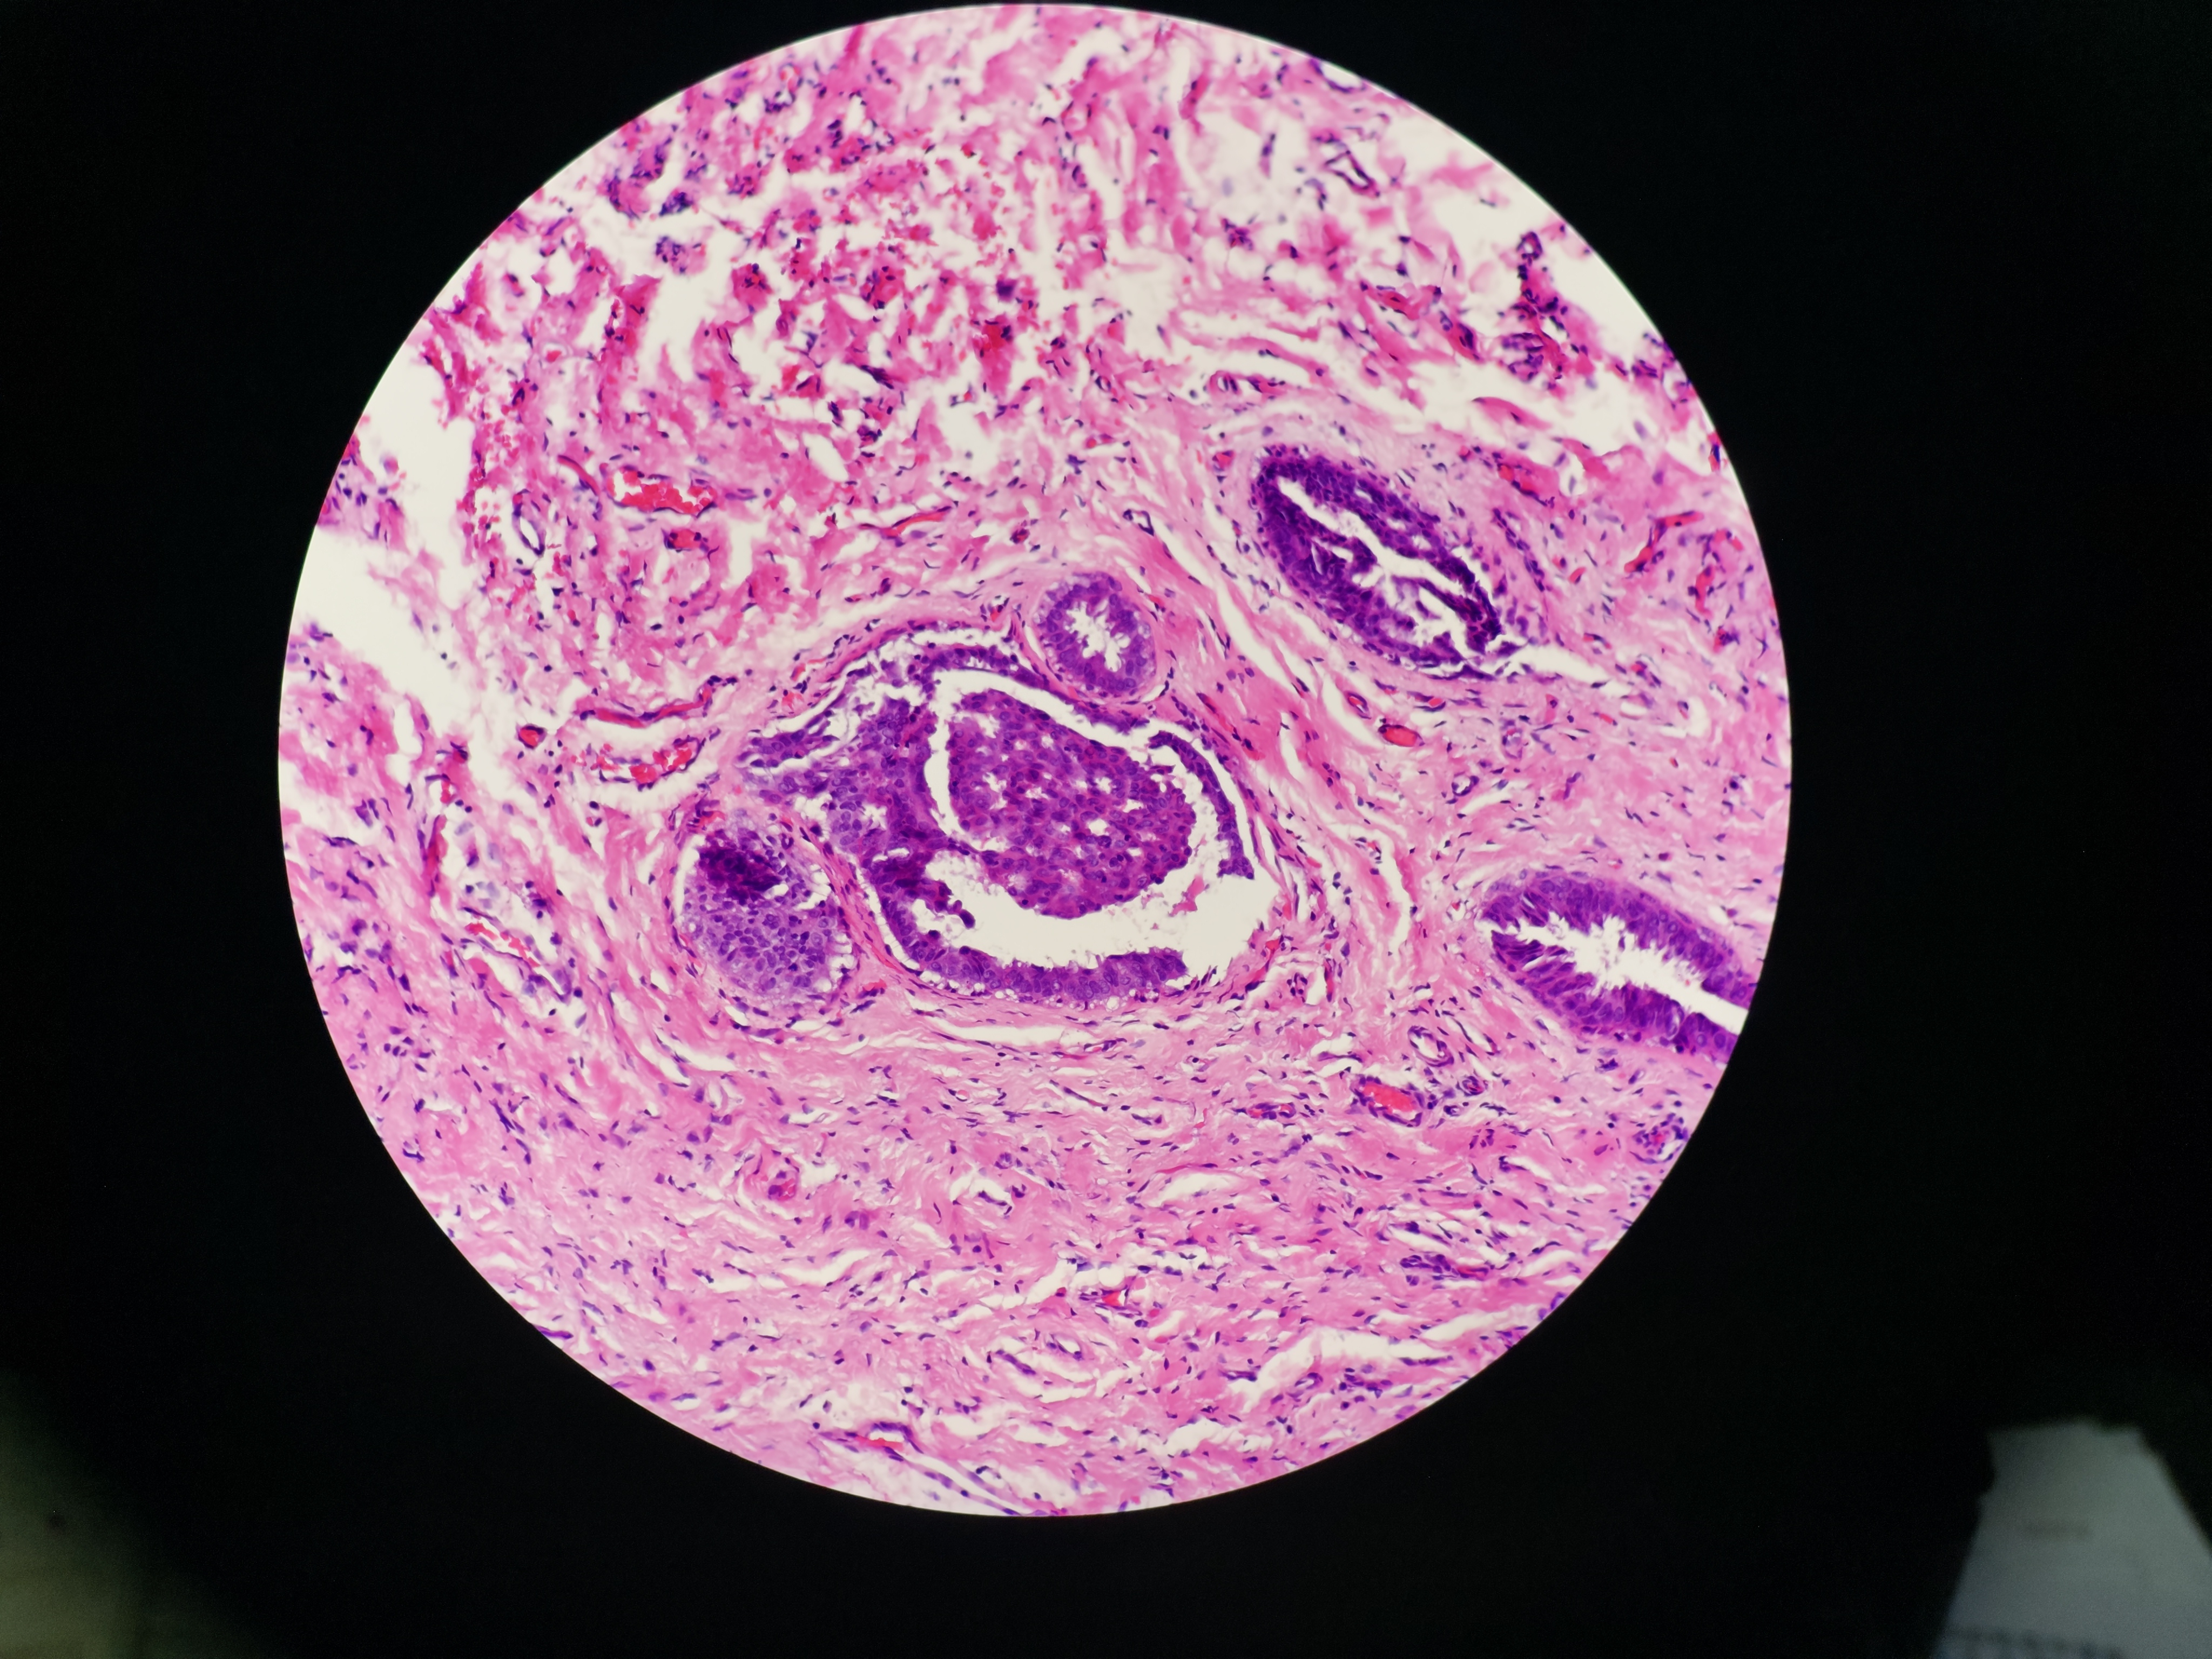

乳腺肿物

性别

女

年龄

38岁

乳腺彩超结果:右乳3点位实性结节BI-RADS 4a

右侧乳腺肿物

灰黄色软组织一块,1.3*1*0.6cm,切面见0.8×0.5×0.5cm的灰白灰红色肿物

各位老师,这个怎么报?报癌?

考虑:UDH